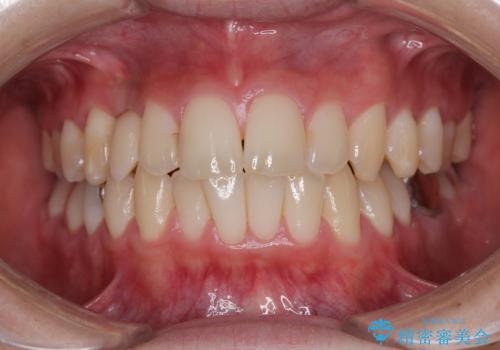

- 20代男性

- 永久歯が生えてこず、欠損になっていることを気にして来院された患者様です。